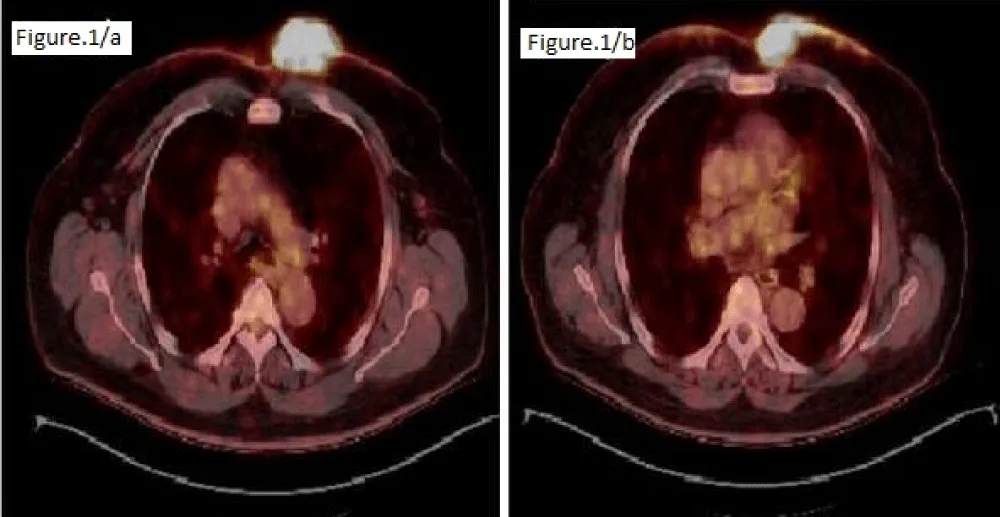

A 65-year-old man presented to the dermatology clinic with complaints of a large erythematous plaque on the anterior chest that had been gradually increasing for two months. He had a history of gout, hypertension, and inflammatory bowel disease, and a history of renal cystectomy and lumbar disc herniation. A biopsy revealed atypical lymphoid infiltration consistent with CD5-negative non-Hodgkin’s B-cell lymphoma, with diffuse CD20 positivity, focal BCL-6 and CD10 positivity, and negative CD34, CD117, TDT, and p63 positivity, extending from the superficial dermis to the subcutaneous fat. The patient was referred to the hematology department. The patient, who had no symptoms, had a PET-CT scan of the left hemithorax. A 57 x 74 mm irregular mass infiltrating the skin/subcutaneous tissue and bilateral (prominent on the left) multifocal skin thickening reaching approximately 9 mm on the anterior chest wall was observed (Figure 1). No systemic involvement was detected, and the patient was referred for RT without considering chemotherapy, phototherapy, or cryotherapy. The patient was treated with the Linac device using an intensity-modulated RT technique using 6 MV photon energy. A boost of 30 Gy/17 fractions was applied to the extensive lesions on the anterior chest wall, and a boost of 20 Gy/11 fractions was applied to the primary mass. Post-treatment physical examination revealed marked regression of the mass and disappearance of the erythematous lesions. A one-month CT scan revealed marked regression of the primary mass and a complete response in the smaller lesions. Six months later, the lesions were reported to have completely disappeared (Figure 2).

Figure 2: PET-CT image obtained at the 6th month after RT; no hypermetabolic nodular formations were observed.